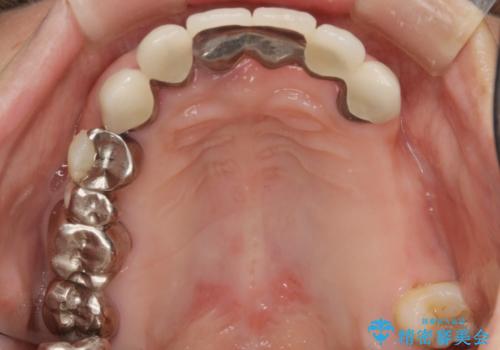

歯周病 全顎治療

- 前歯の見た目、入れ歯による噛めないことの改善を求めて来院されました。

検査により全顎的な歯周病治療、欠損のインプラント補綴、根管治療が必要な状態であることをお伝えし、治療を計画します。